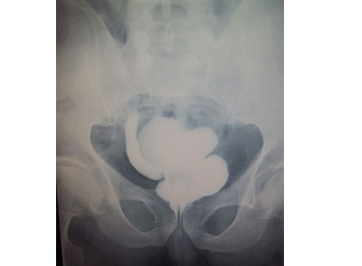

BÖBREK-ÜRETER-MESANE TAŞLARININ CERRAHİ YÖNTEMİ İLE TEDAVİSİ

Pcnl tedavisinde ortalama kan kaybı 2. 8 g/dl hemogobindir. Bu yöntem ne kadar efektif ve minimal invazif bir yöntem olarak kabul edilsede çeşitli araştırmalada yüksek komplikasiyonlar bildirilmiştir.